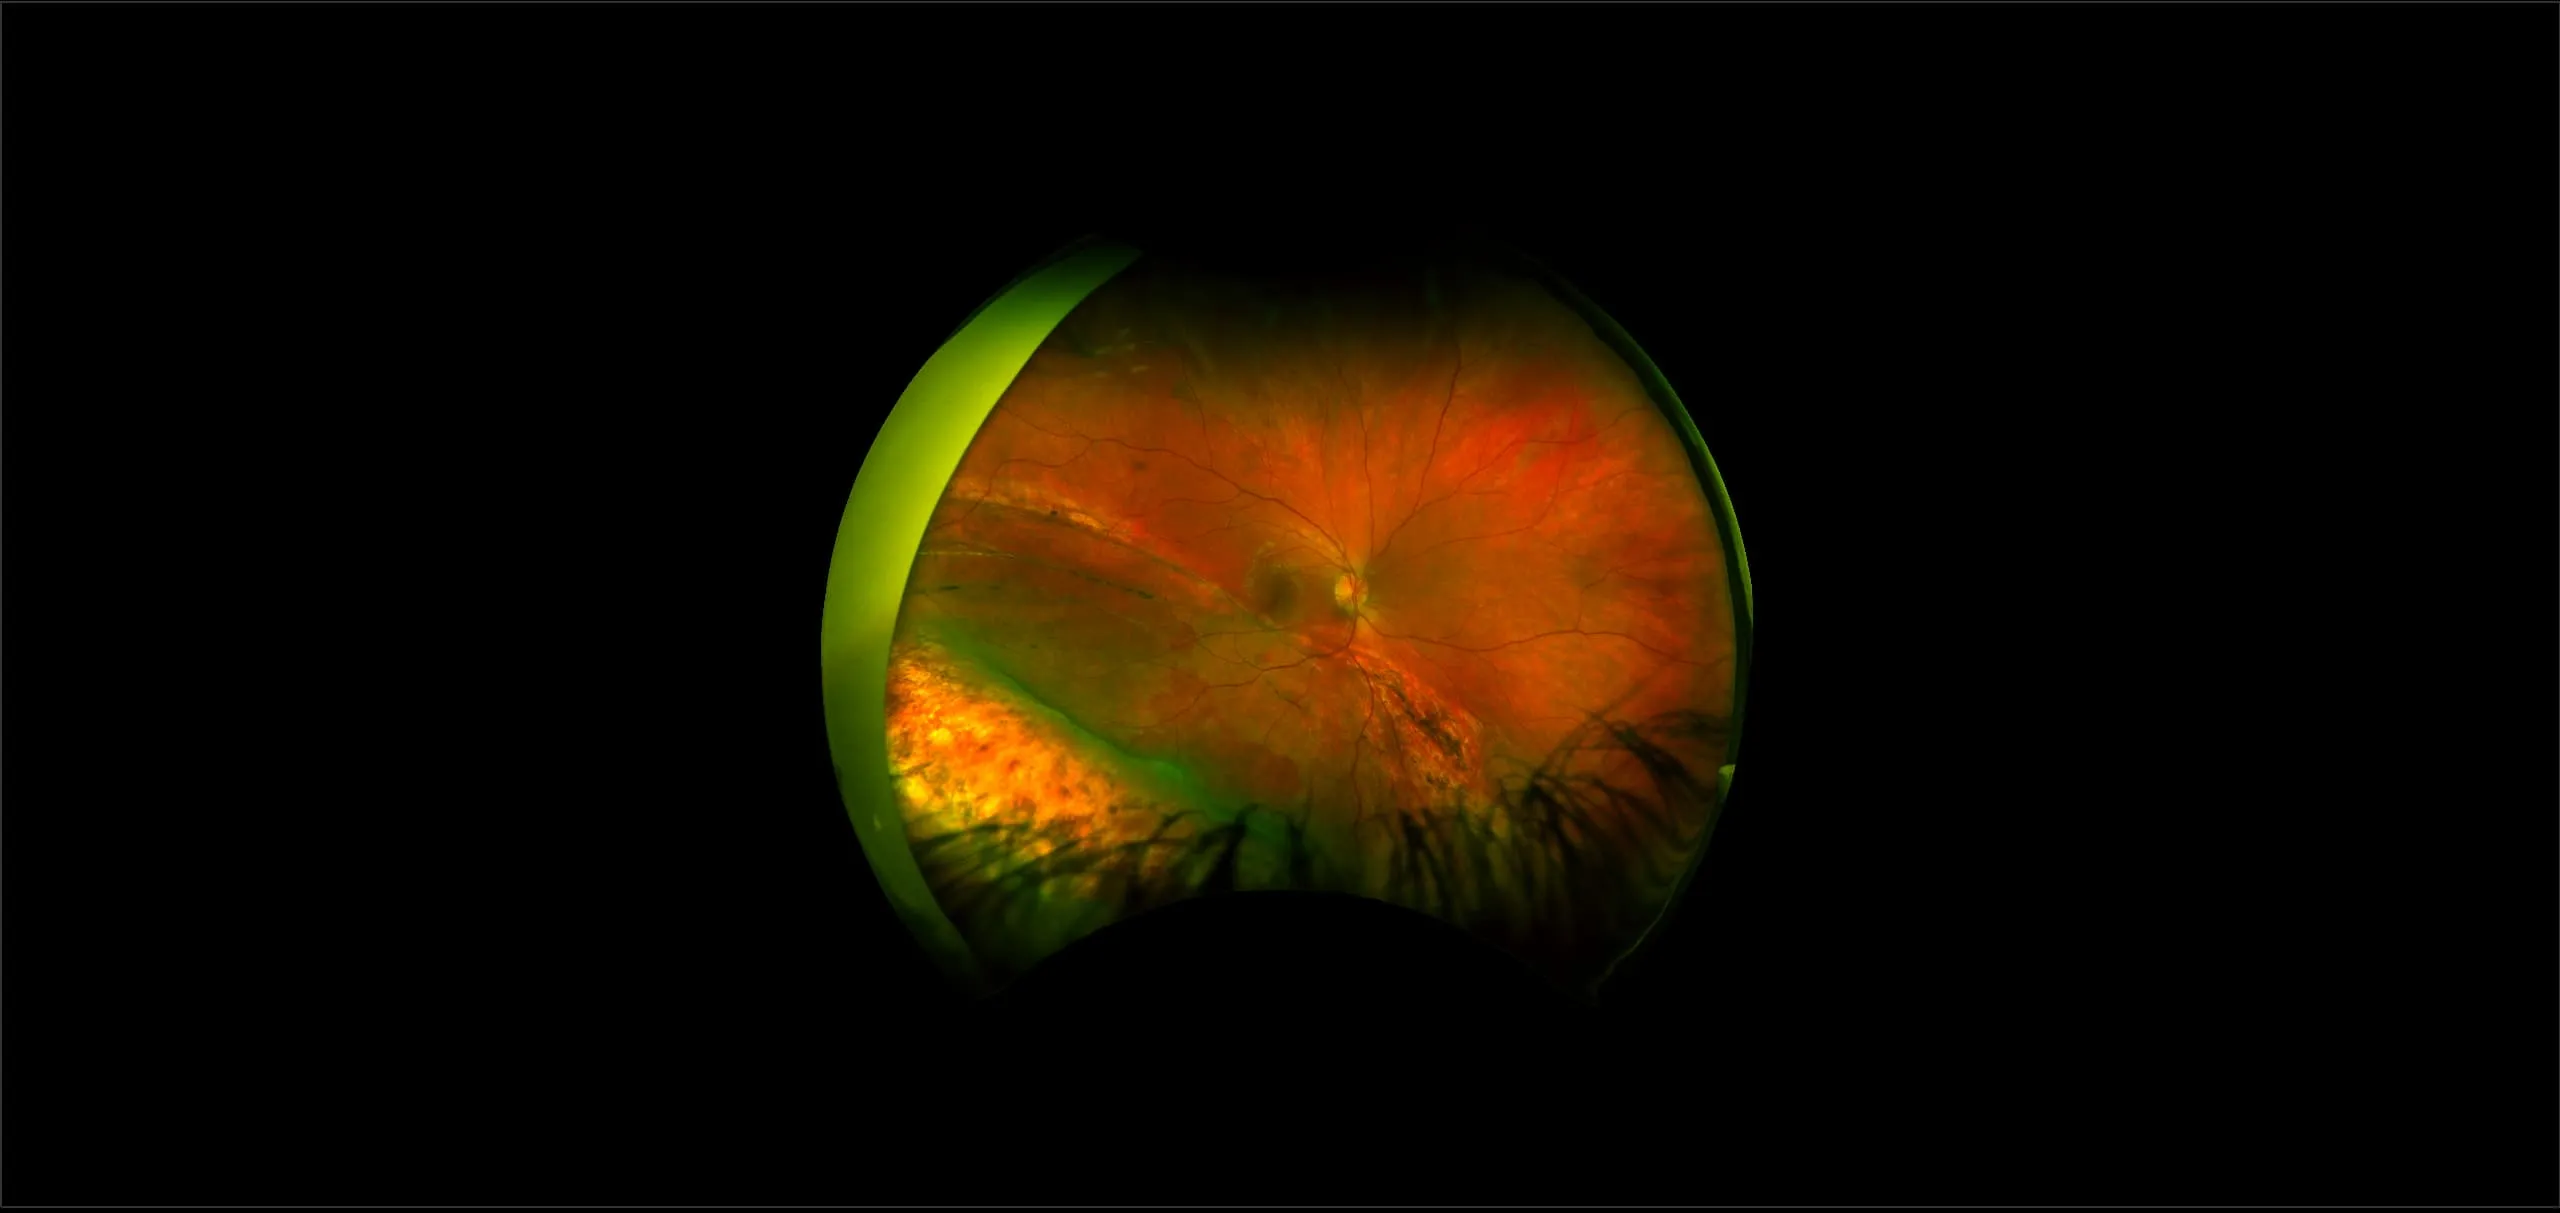

optomap® Recognizing Pathology

This material is designed as a searchable reference resource to support clinical decision-making. The information contained here should be used as general guidance when viewing optomap and OCT images from Optos devices. The differential diagnosis should be made under the direction of the responsible physician. These images were taken on the latest ultra-widefield optomap devices.

The Cases and Images

optomap Recognizing Pathology is searchable by pathology and/or optomap image modality. You may search by multiples of each selection. Each individual case is represented by the accompanying thumbnail image. Most cases include several different optomap image modalities. To view a full description of the case, please click on the thumbnail. Each image in the case will be made available through our OptosAdvance software which provides multi-dimensional visualization of digital images to aid in the analysis of anatomy and pathology. Support and pathology definitions can be found by selecting one of the buttons, above. Should you have questions, please complete the form below.